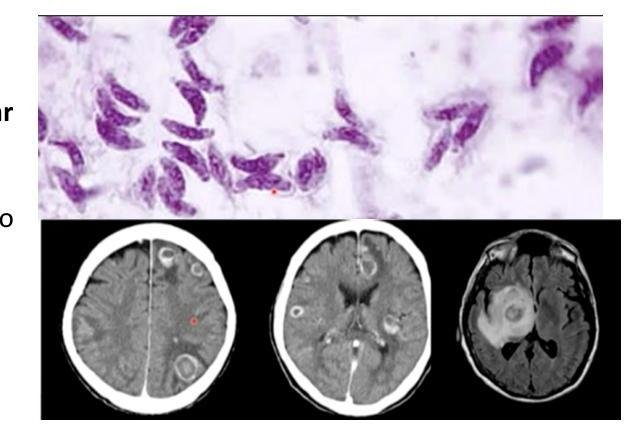

# TOXOPLASMOSIS ## DEFINICIÓN La toxoplasmosis es la infección por **Toxoplasma gondii**. Sus síntomas van desde ninguno hasta **adenopatías** (**enfermedad semejante a Mononucleosis**) o incluso una enfermedad del **sistema nervioso central (SNC)** peligrosa para la vida o con compromiso de otros órganos en pacientes **inmunodeficientes**. Puede desarrollarse **encefalitis** en pacientes con **SIDA** y recuentos bajos de **CD4**. La **infección congénita** provoca **retinocoroiditis**, **convulsiones** y **discapacidad intelectual**. ## FISIOPATOLOGÍA Los únicos **huéspedes definitivos** documentados de T. gondii son los miembros de la familia de los **felinos** (**gatos domésticos** y otros animales relacionados). 1. Los ovoquistes se descaman y se eliminan con las heces del gato. Se excreta una gran cantidad, aunque en general durante 1 o 2 semanas. Los ovoquistes tardan entre 1 y 5 días en adquirir capacidad infecciosa. 2. Los gatos se reinfectan al ingerir los ovoquistes esporulados. 3. El suelo, el agua, la materia vegetal o el área donde duerme el gato se contaminan con ovoquistes. Los huéspedes intermediarios en la naturaleza (p. ej., aves, roedores, animales salvajes, animales de granja) se infectan tras ingerir materiales contaminados. 4. Los ovoquistes se convierten en taquizoítos poco después de su ingestión. 5. Los taquizoítos se diseminan por todo el cuerpo y forman quistes tisulares en el tejido nervioso y muscular. 6. Los gatos se infectan tras consumir huéspedes intermediarios con quistes tisulares. 7. Los seres humanos pueden infectarse al consumir carne mal cocinada que contenga los quistes tisulares. 8. Los seres humanos pueden infectarse al ingerir alimentos o agua contaminados con heces de gatos o con otros materiales contaminados por heces (p. ej., suelo) o por el contacto con el área donde duerme un gato doméstico. 9. Rara vez, la infección humana se debe a una transfusión de sangre o a un trasplante de órgano. 10. Rara vez, se produce la transmisión transplacentaria de madre a feto. 11. En el huésped humano, los parásitos forman quistes tisulares, sobre todo en el músculo esquelético, el miocardio, el encéfalo y los ojos; estos quistes pueden permanecer en el cuerpo toda la vida del huésped y pueden reactivarse si la inmunidad del huésped se compromete.  # CLÍNICA ## TOXOPLASMOSIS AGUDA La infección aguda suele ser **asintomática**, pero entre el 10 y el 20% de los pacientes desarrolla **adenopatías cervicales o axilares bilaterales indoloras**. Unos pocos de estos individuos también experimentan un **síndrome seudogripal leve** caracterizado por **fiebre**, **malestar general**, **mialgias**, **hepatoesplenomegalia** y, con menor frecuencia, **faringitis**, que puede simular una **mononucleosis infecciosa** e incluir **linfadenitis**. La **linfocitosis atípica**, la **anemia leve**, la **leucopenia** y el **aumento leve de las concentraciones de enzimas hepáticas** son habituales. El síndrome puede persistir durante semanas, pero casi siempre es **autolimitado**. ## TOXOPLASMOSIS DEL SNC La mayoría de los pacientes con **SIDA** u otras **inmunodeficiencias** que desarrollan **toxoplasmosis** se presentan con **encefalitis** y **tumores intracraneales con refuerzo de contraste de forma anular** que se observan en la **TC** con contraste. El riesgo es mayor en las personas con recuentos de **CD4** < 50/µL; la **encefalitis toxoplásmica** es rara cuando los recuentos de **CD4** son >200/µL. Los pacientes típicos experimentan **cefalea**, **alteración del estado mental**, **convulsiones**, **coma**, **fiebre** y a veces **deficiencias neurológicas localizadas**, como pérdida motora o sensitiva, parálisis de los nervios craneales, trastornos visuales y convulsiones focales. ## DIAGNÓSTICO 1. Pruebas **serológicas** (**IgG** e **IgM**). Un **IgG** negativo es casi seguro para descartar infección. 2. Evaluación **HISTOPATOLÓGICA** de las **BIOPSIAS**. 3. Ensayos basados en **PCR** de **sangre**, **LCR**, **tejido** o, durante el embarazo, **líquido amniótico**. 4. **RMN**/**TAC** - **REALCE EN ANILLO**. ## TRATAMIENTO  1ª elección: **Pirimetamina** y **Sulfadiazina** Se agrega **Leucovorina** o **Ácido FOLÍNICO** (para prevenir la **supresión de la médula ósea**) - Alternativa: **TRIMETOPRIM/SULFAMETOXAZOL A DOSIS ALTAS** (es el utilizado en **Mx**) 2ª elección: **Clindamicina** o **Atovacuona** + **Pirimetamina** - Cuando el paciente es **alérgico a las sulfonamidas** o no tolera la **sulfadiazina** El tratamiento de la toxoplasmosis no está indicado para pacientes **inmunocompetentes** que son **asintomáticos** o tienen una **infección aguda leve no complicada**; solo se requiere tratamiento cuando la **enfermedad visceral** está presente o los **síntomas son graves o persisten**. ## TRATAMIENTO DE ASINTOMÁTICOS: - **Recién nacidos** - **Mujeres embarazadas con toxoplasmosis aguda** - **Pacientes inmunocomprometidos**